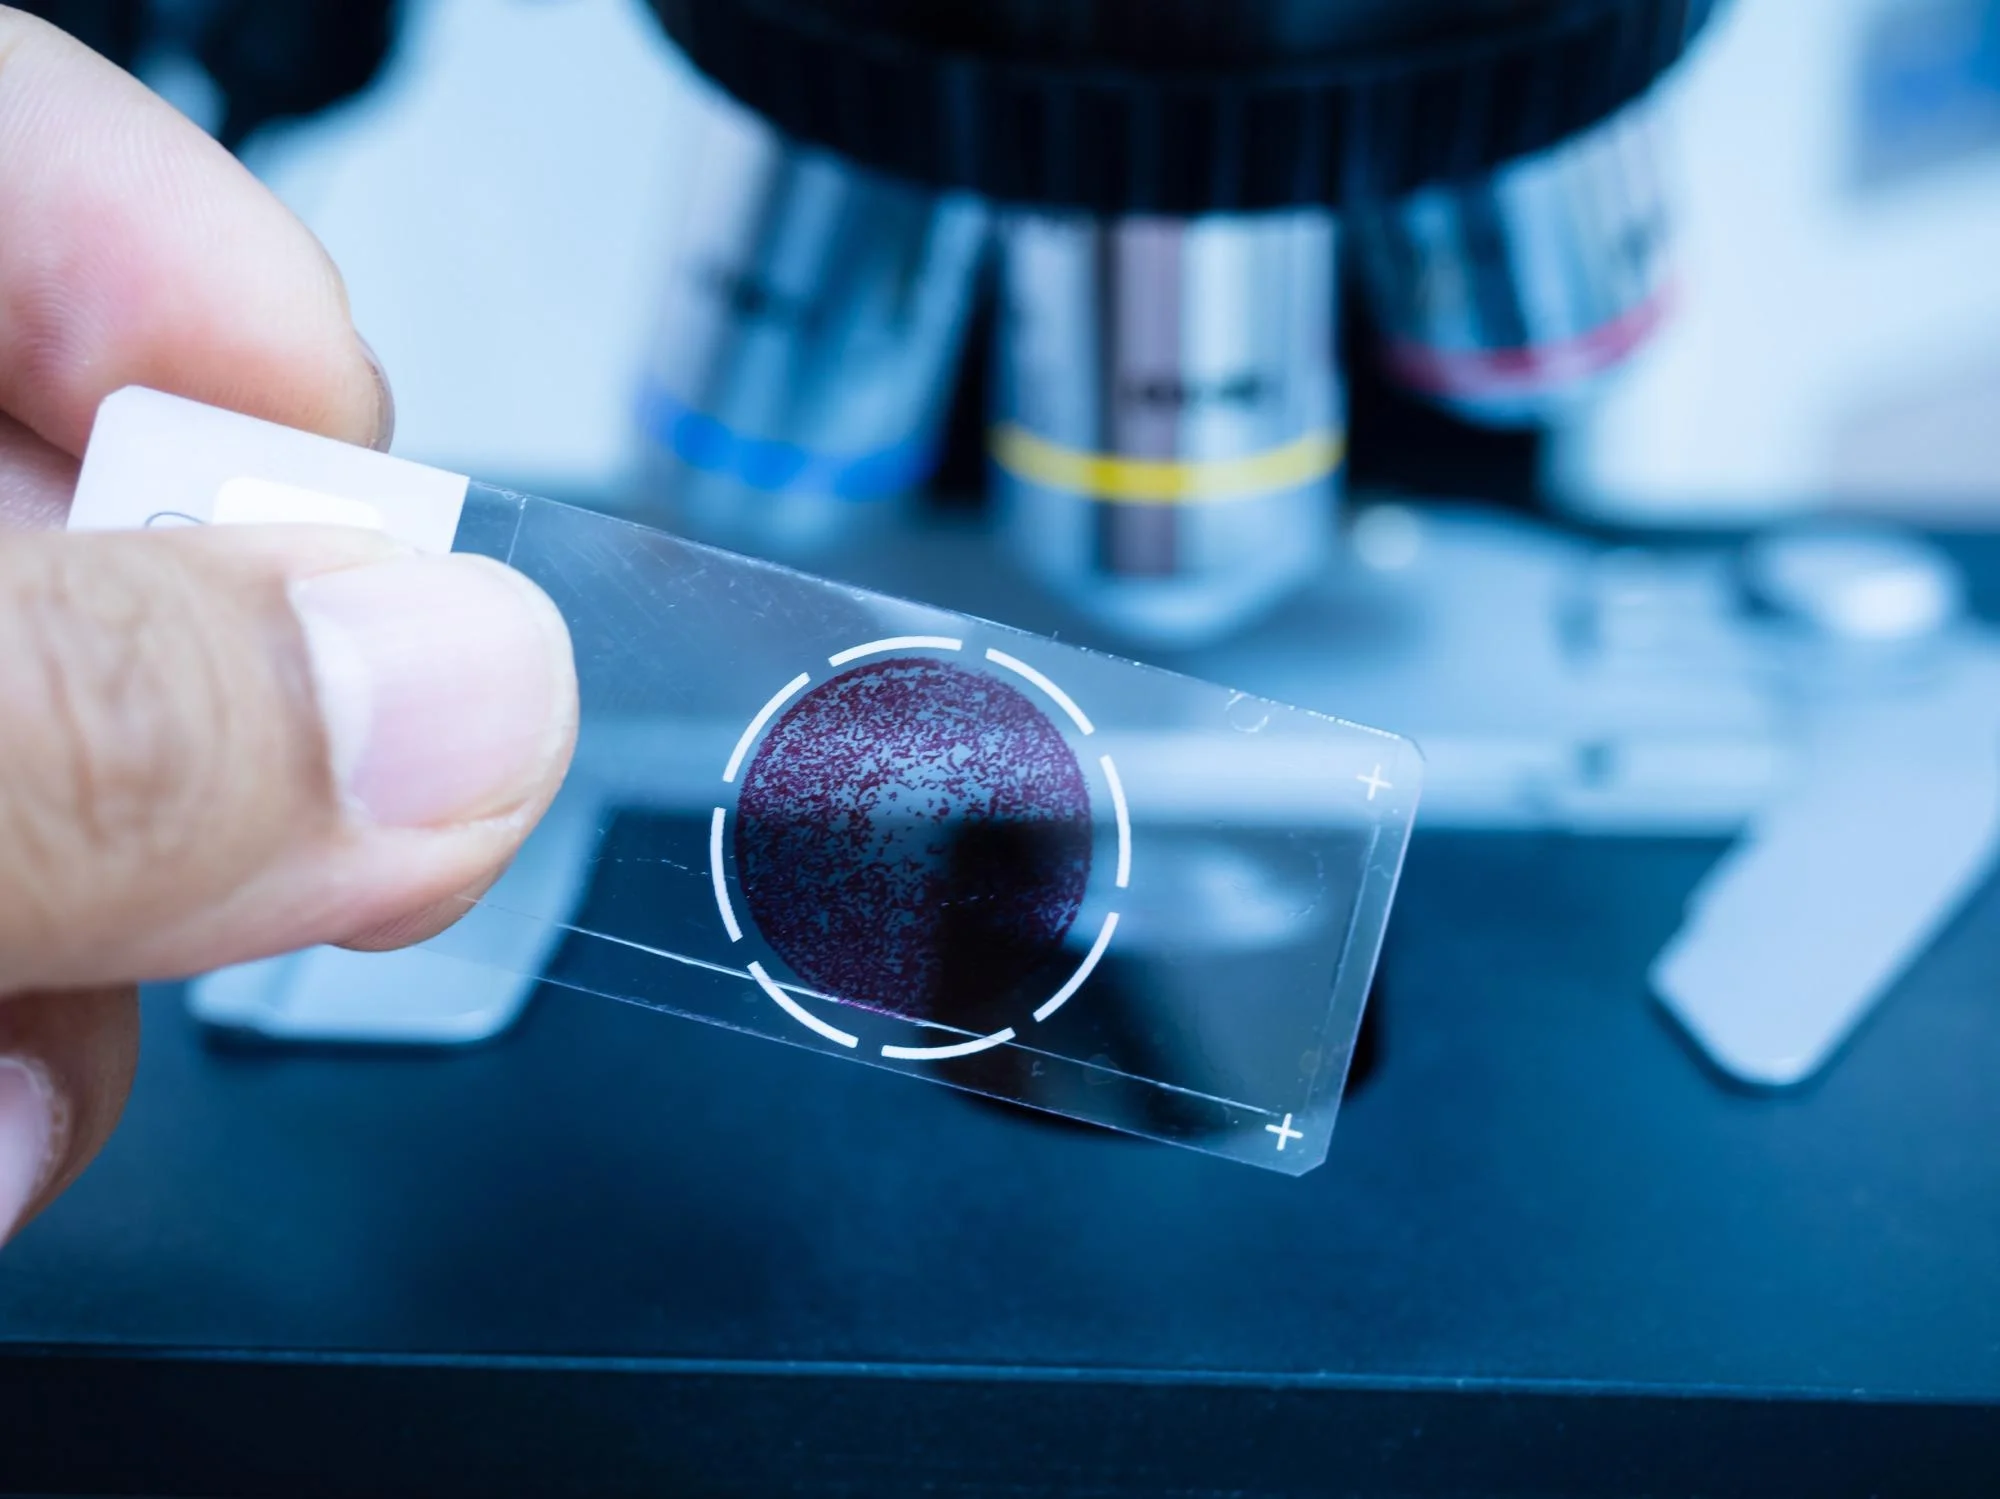

We are a registered pathology collection site and we endeavour to have a pathology collector on site for all of our opening hours. Our dedicated team of nurses and pathology collectors will be able to assist you with all of your pathology needs.